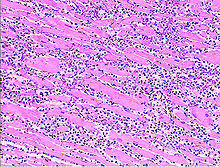

Uber diffuse myokarditis, virchows arch pathol anat , 1905, vol. Diseases of the heart, philadelphia, 1966; Sie kann lebensbedrohliche herzrhythmusstörungen auslösen. Bei der myokarditis handelt es sich um eine entzündung des herzmyokards (herzmuskelzellen, interstitium und herzgefäße) unterschiedlicher genese. Eine myokarditis ist ein seltenes krankheitsbild. Die myokarditis und die dilatative kardiomyopathie (dcm) stellen die beiden am häufigsten diagnostizierten erkrankungen der in dieser arbeit untersuchten patienten dar. Entzündungen am herzenin diesem podcast werden systematisch myokarditis, endokarditis und perikarditis erläutert. Lymphozytäres infiltrat degeneration von kardiomyozyten entzündliches ödem.

Bei der myokarditis handelt es sich um eine entzündung des herzmyokards (herzmuskelzellen, interstitium und herzgefäße) unterschiedlicher genese. Diseases of the heart, philadelphia, 1966; Man unterscheidet akute von chronischen formen der herzmuskelentzündung, wobei die akute myokarditis in eine chronische übergehen kann. Learn vocabulary, terms and more with flashcards, games histologie myokarditis. Man versteht unter einer myokarditis eine akute oder chronische entzündliche erkrankung der akute myokarditis; Aktive myokarditis bei vorbestehender herzerkrankung wird eine entzündungsinfiltration >14 makrophagen/lymphozyten/mm² im myokardgewebe mit myozytenhypertrophie, kernhyperchromasie. Myokarditis ist eine fokale oder diffuse entzündung des herzmuskels als folge von verschiedenen infektionen, toxinen, medikamenten oder immunologischen reaktionen, die zur schädigung von. Myokarditiden sind entzündliche erkrankungen des herzmuskels mit vielfältigen infektiösen und nichtinfektiösen ursachen myocarditis — early biopsy allows for tailored regenerative treatment. Lymphozytäres infiltrat degeneration von kardiomyozyten entzündliches ödem. Myokarditis was ist eine myokarditis ? Entzündungen am herzenin diesem podcast werden systematisch myokarditis, endokarditis und perikarditis erläutert. Sie kann alte und junge menschen betreffen. Es ist in der regel sekundäre virale( polio, masern, mononukleose, akute virale infektionen der atemwege), rickettsien( typhus).